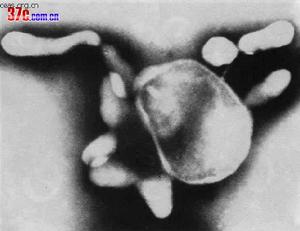

解脲脲原體(M.urealyticum)為脲原體屬中唯一的一個種,因生長需要尿素而得名。菌落微小,直徑僅有15~25um,須在低倍顯微鏡下觀察,故舊稱T株(tinystrain)。菌落表面有粗糙顆粒,在合適條件下可轉成典型的荷包蛋樣菌落。生長需要膽固醇和尿素,分解尿素為其代謝特徵,產生氨氮,使培養基pH上升,導致自身死亡。